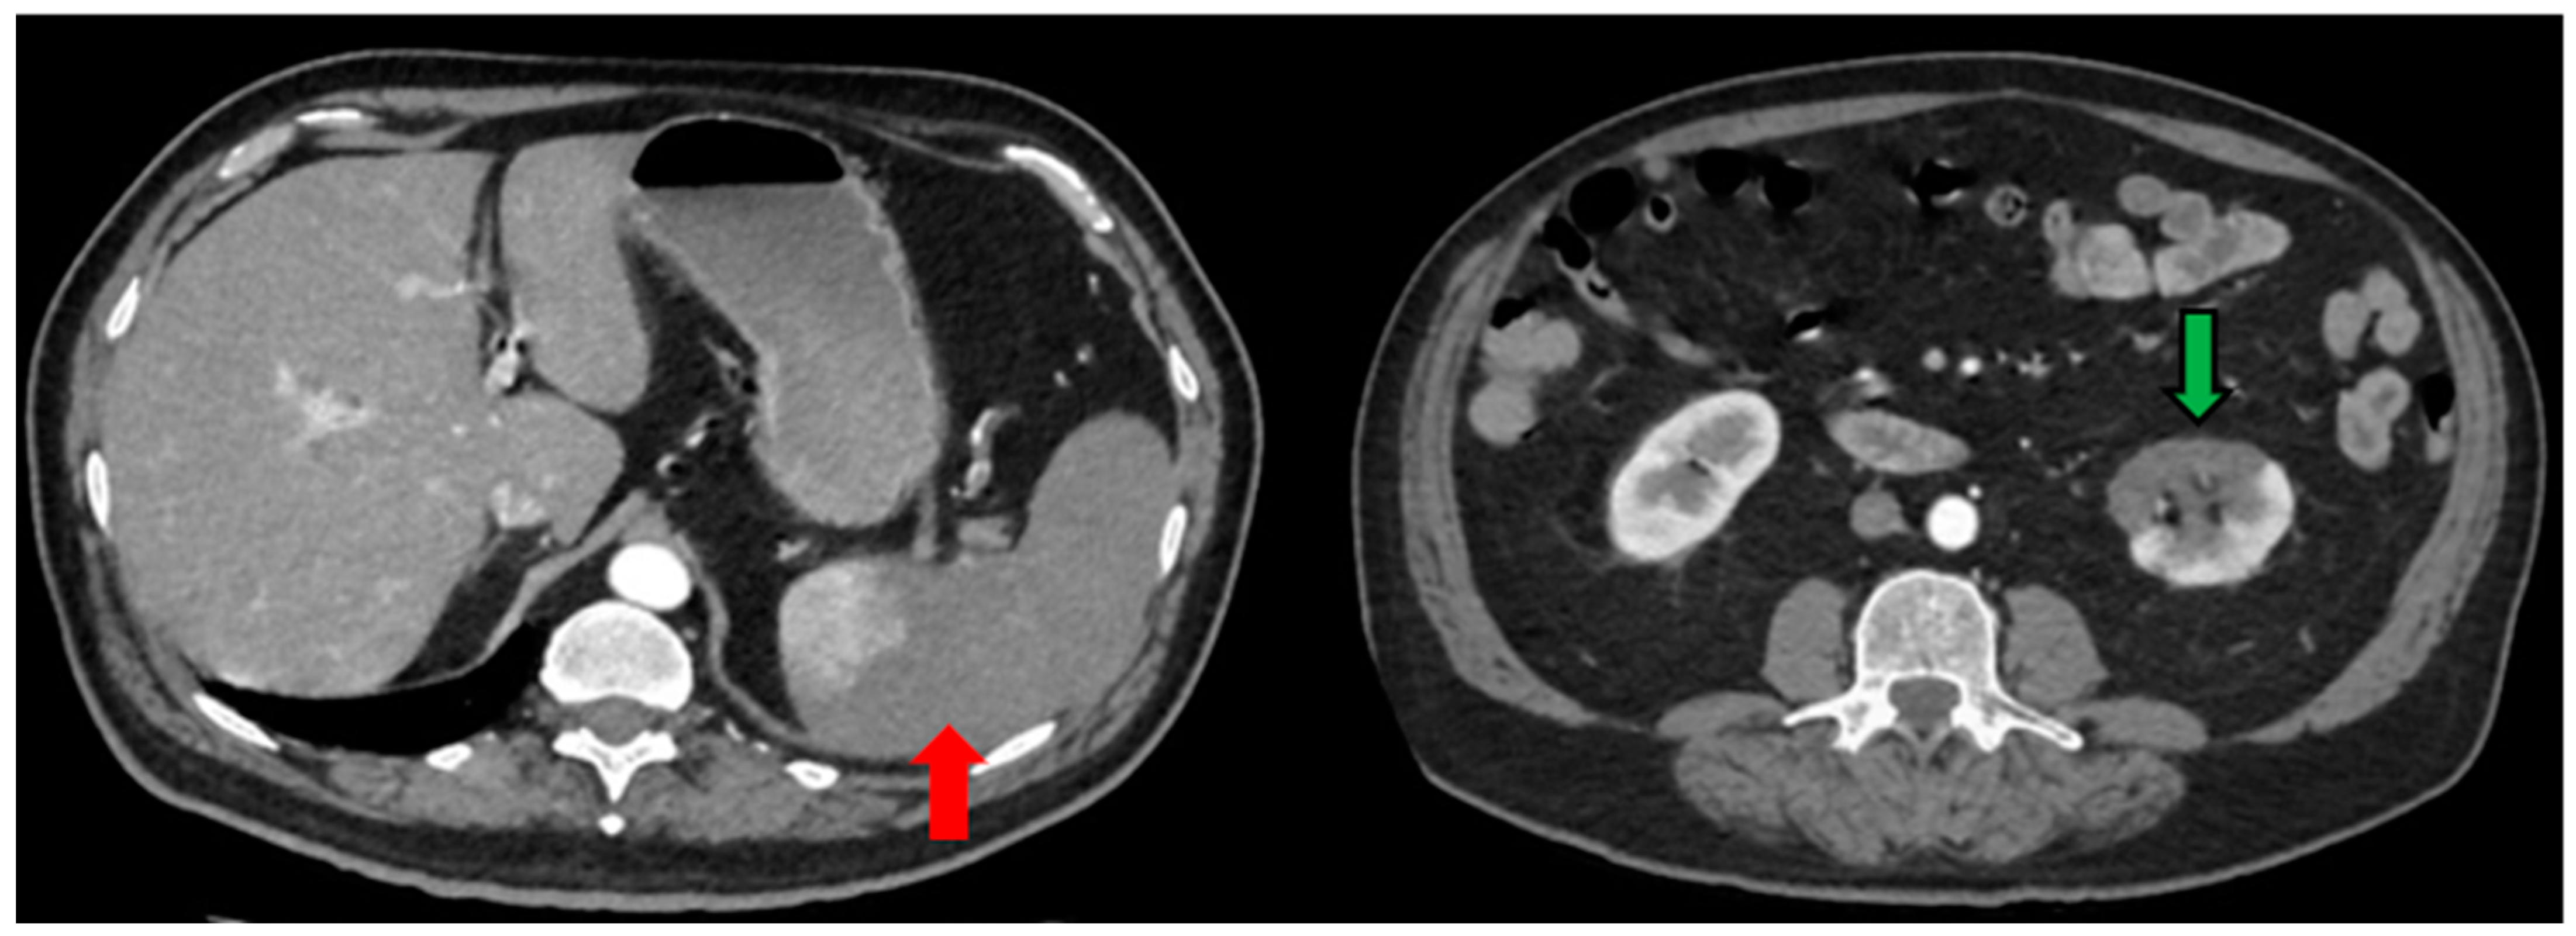

| Day 6 | Blood exams: 23,000 WBCs, LDH 1892 U/L, d-dimers 4.3 mg/L CTPA: Bilateral ground glass opacities, no evidence of pulmonary embolism, thrombi up to 5 mm in the thoracic aorta Abdominal and pelvic CT scan: Splenic infarct, thrombosis of splenic artery and vein, renal infarct at the left lower lobe. Enoxaparine at therapeutic dose (8.000 IU twice daily), acetylsalicylic acid 80 mg |